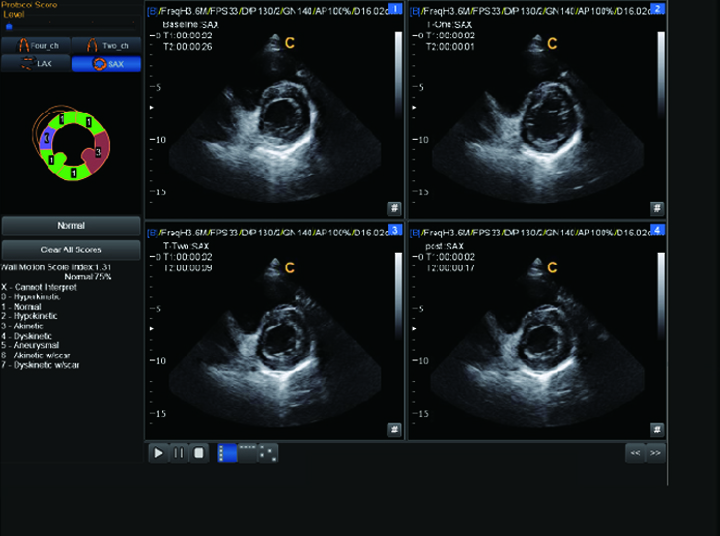

Echo Estés

Strain y Strain Rate